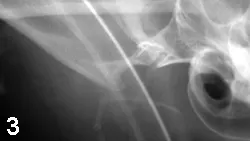

The ProcedureThe TMJ was approached through a lateral skin incision along the caudoventral margin of the zygomatic arch. A periosteal elevator was used to lift the condylar head (Figure 1; black arrow) into the temporal fossa (white arrow). The masseter muscle was reflected ventrally, and the damaged TMJ joint capsule was visualized by having an assistant open and close the jaw. The dorsocranially deviated condyle was reduced into the temporal fossa. A small hole was drilled through the lateral condyle and fossa by using a no. 1 round bur in a high-speed dental handpiece. A 4-0 nonresorbable nylon was threaded through the predrilled holes, and a simple interrupted knot was tied (Figure 2). Because there was no overlying musculature around the severely damaged joint capsule, imbrication was impossible. A postreduction extraoral radiograph indicated successful reduction (Figure 3).